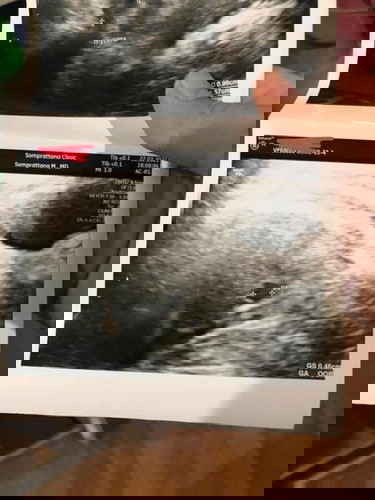

ก้อนเนื้อในมดลูก

ท้องได้ประมาณ6สัปดาห์เจอก้อนเนื้อในมดลูก3ก้อน ขนาด2ซม ก้อนนึง และขนาด1ซม สองก้อน เลยทำให้ถุงตั้งครรภ์เกาะต่ำ ซาวด์ครั้งแรกยังไม่เจอตัวเด็กคะ ใครมีประสบการณ์ก้อนเนื้อในมดลูกขณะท้องบ้างคะ มาแชร์ประสบการณ์ให้ฟังหน่อยคะ หมอบอกว่า1ใน3เท่านั้นที่ก้อนเนื้อจะโตเร็วกว่าเด็ก #ท้องแรกคะ #แอบกังวลกลัวน้องจะไม่แข็งแรง #ขอคำแนะนำค่ะ #ขอบคุณล่วงหน้านะคะ